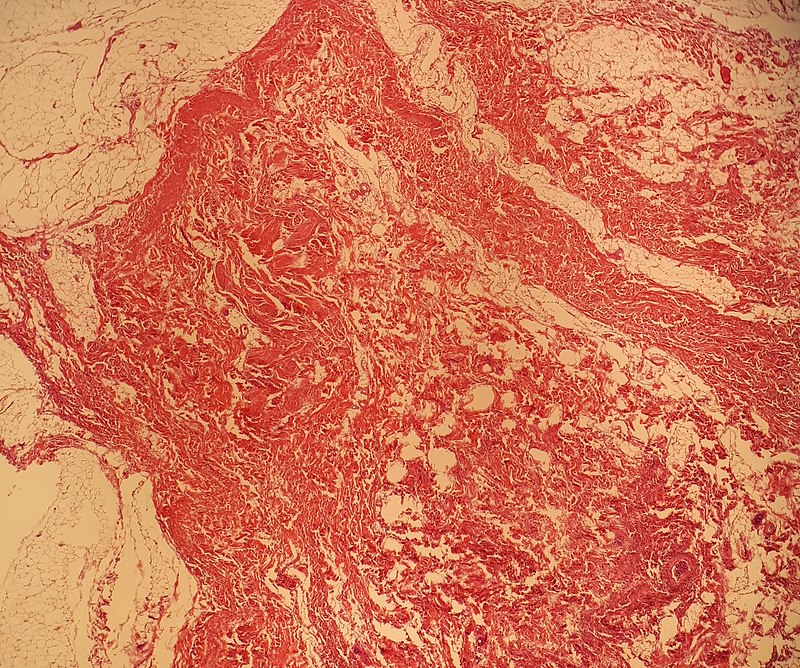

Rhabdomyosarcoma

Rhabdomyosarcomas are malignant tumors composed mainly of skeletal muscle.

Rhabdomyomas typically effect skeletal muscle, or occasionally hollow organs like the bladder or uterus.

Diagnosis is made by histology showing malignant skeletal muscle with rhabdomyoblasts, which are the characteristic cells of rhabdomyosarcoma.

Pathology stains for rhabdomyosarcoma will be desmin stain positive.

Rhabdomyosarcomas often involve the head and neck in the majority of patients, but the vagina is the classic site in young girls.